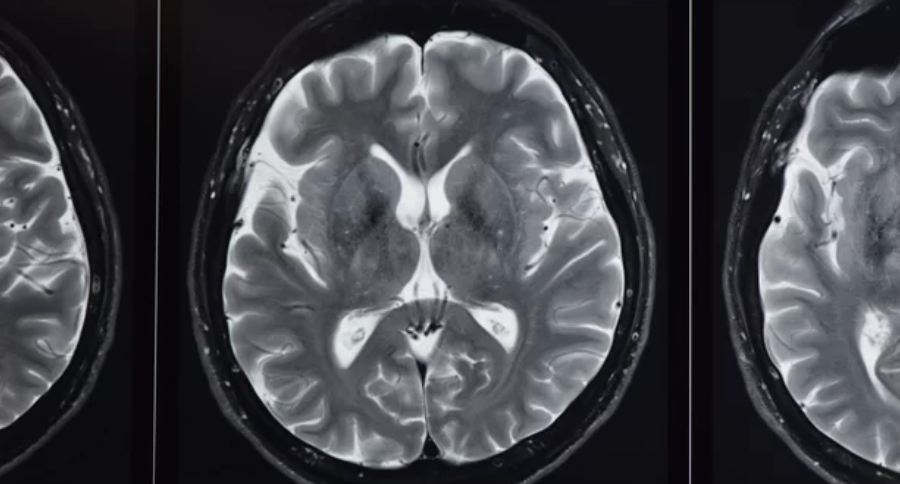

Transforming Diagnostic Imaging with Advanced MRI

Advanced MRI technology is improving the speed, accuracy, and scope of diagnostic imaging. It supports detailed views of the human body and helps doctors make better decisions. The integration of AI and new hardware has also enhanced how hospitals manage MRI scans.

Recent advancements in MRI technology include faster scan times and improved image quality. New machines use stronger magnets and better software algorithms to capture clearer, more detailed images.

Next-generation MRI offers more precise diagnoses, especially in complex cases like cancer or neurological diseases. It helps differentiate between healthy and diseased tissues with better contrast.